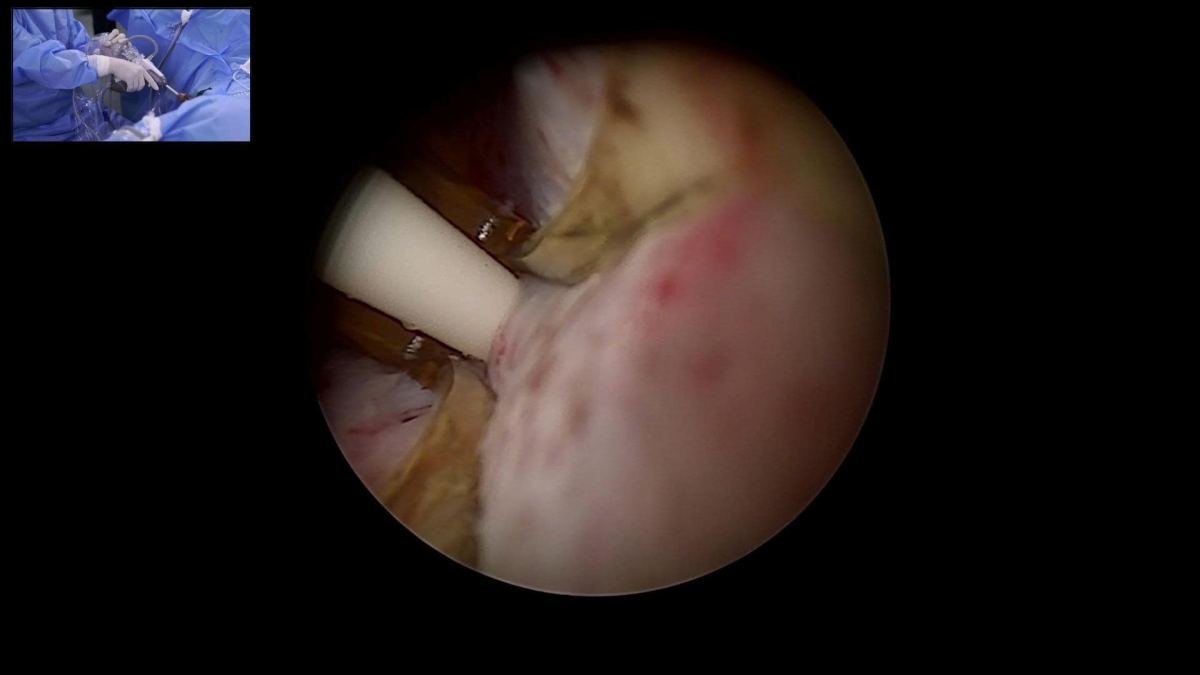

Nội soi trong quá trình thực hiện liệu pháp nhiệt hơi nước (Rezūm) tại Bệnh viện Bạch Mai